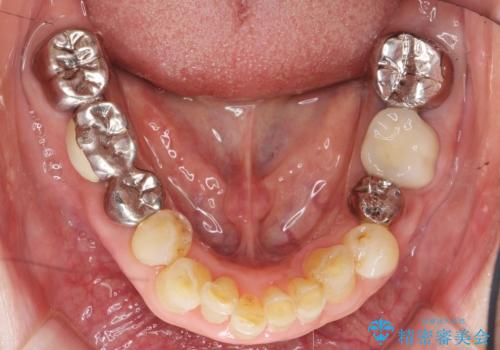

保存不可能な奥歯(左下6)を抜歯し、機能していない親知らず(左下8)の移植を行いました。

移植後、生着を待って根管治療及び補綴修復を行いました。

機能していない親知らずを用いて咬合を回復することができ、喜んで頂けました。

患者様のモチベーションが上がり、他の部位の治療も希望され現在治療中です。